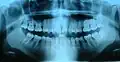

Ортопантомограмма зубов -